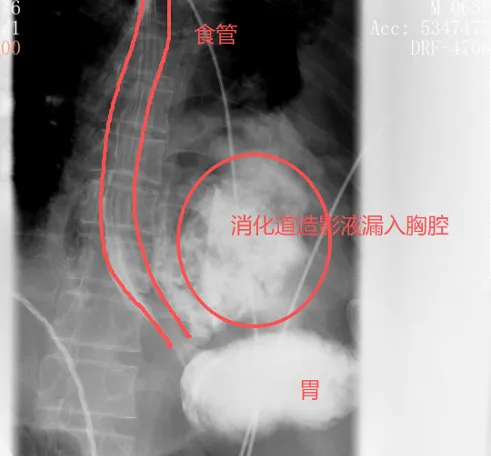

很快,口服钡餐的结果印证了他的判断:钡剂从食道下段的裂口处大量漏出,直接进入了左侧胸腔。

自发性食管破裂,也称为Boerhaave综合征,是胸外科最凶险的急症之一,发病急、进展快、死亡率极高。而此时,距离张叔发病还不到24小时——这是救治的黄金窗口期。